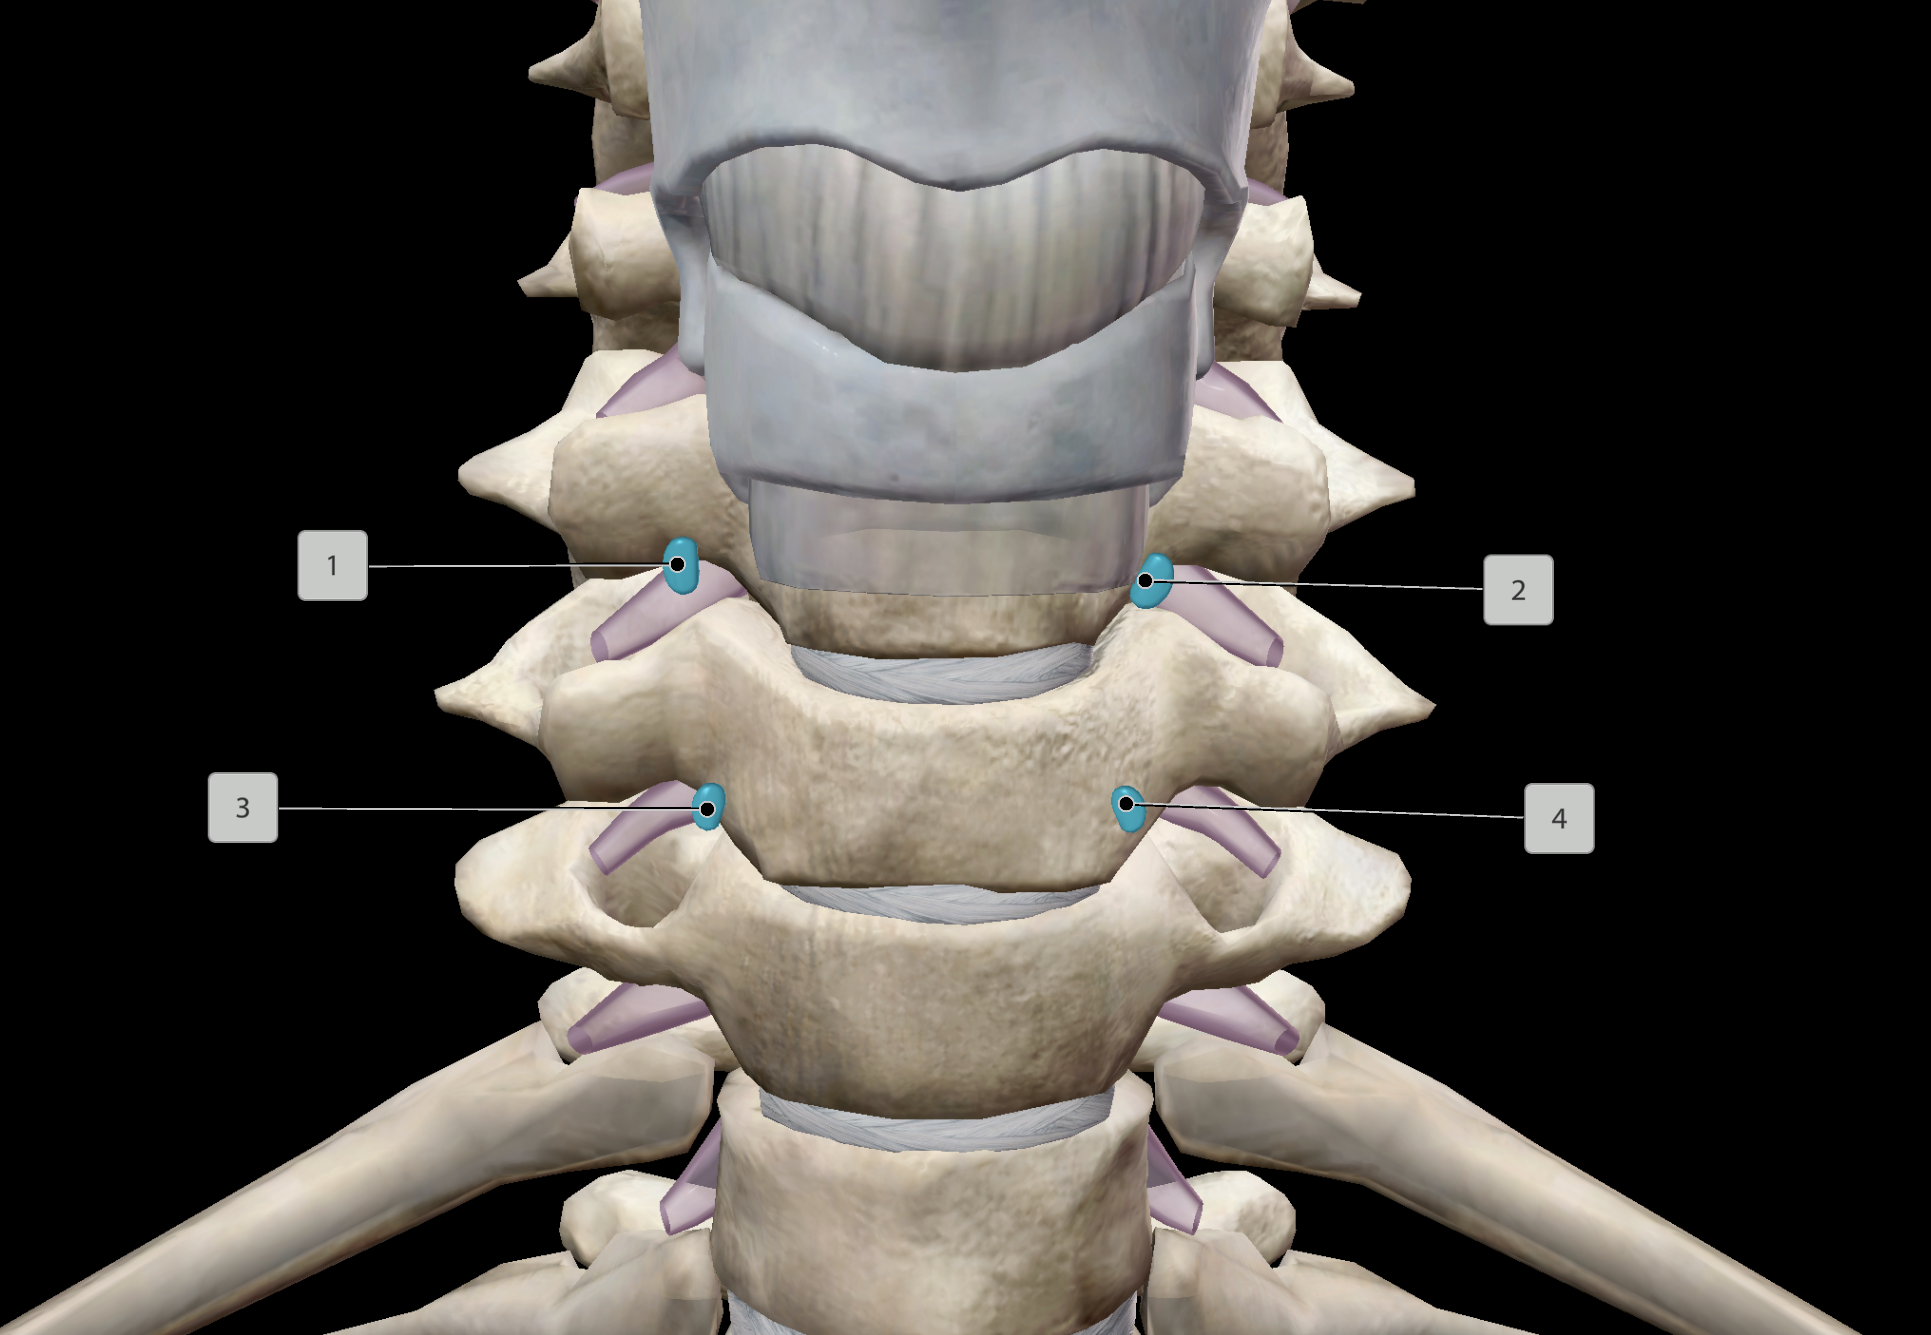

AV Node

SA Node